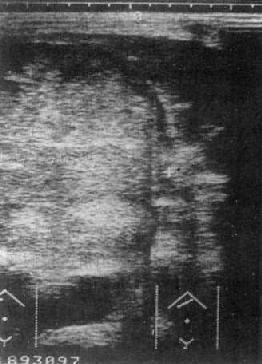

原发性肝癌:USG是影像学诊断中的首选方法。声像图上肝癌表现为聚集成团的强回声区,光团强弱分布不均,边比缘不规则。光点常粗糙明亮,与正常肝组织有明显差别。肿瘤区下方的正常肝组织回声强度降低,系因肝癌引起的超声衰减所致(图4-3-2)。

图4-3-2 肝癌(巨块型)

另一种表现是病变区以低声为主,该区光点稀疏。肿瘤区后方边缘无增强效应,可与囊肿鉴别。在弥漫型肝癌可见到弥漫分布的点片状、粗细不规则光点或光斑,诊断较难。